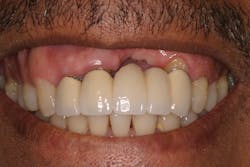

• site development to increase hard and soft tissue for pontic sites in fixed bridge prosthetics (figures 9–14);• correcting bone defects impinging upon anatomical structures after tooth extraction, such as oroantral communication (figure 18); and